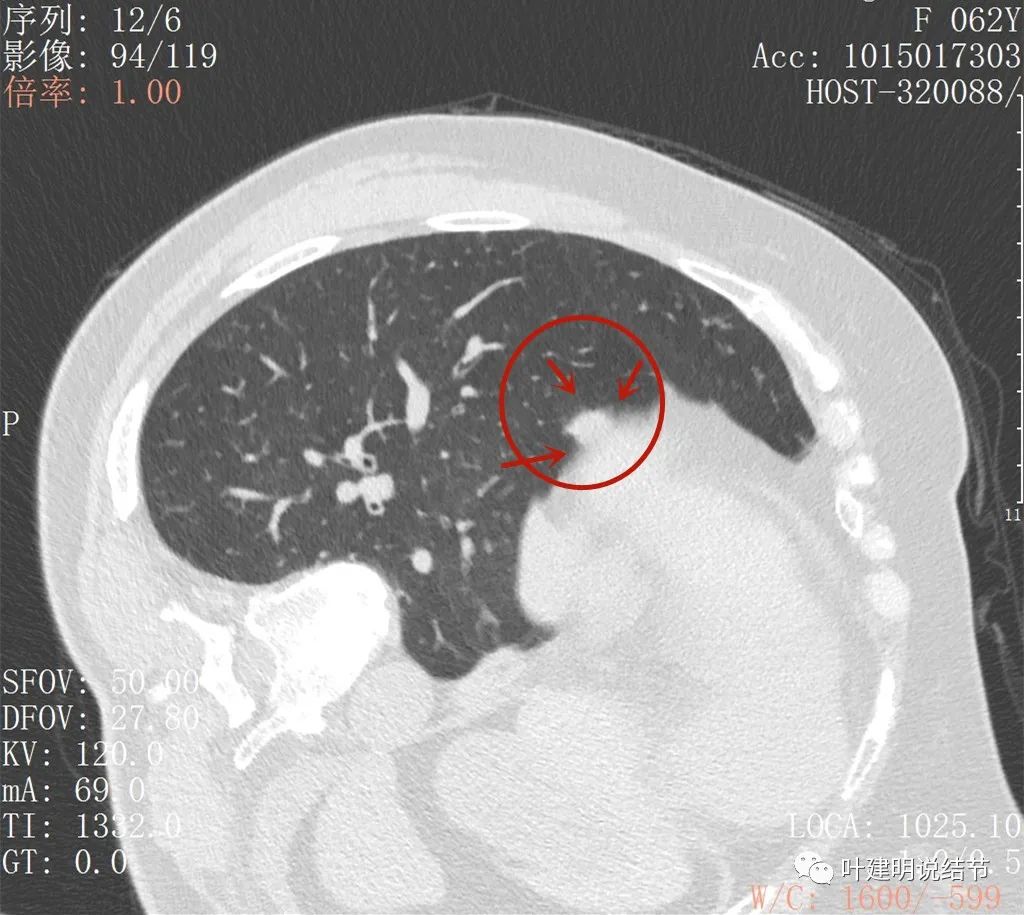

这是最近一次平扫的片子,此结节感觉有膨胀感,边界较清,位于肺底,贴膈面。我们从数次复查的对比,看来该结节是缓慢进展的,不吸收也不钙化,也不是纤维增生或条索状瘢痕的样子。在门诊我仔细对比了这些不同时间的片子后,认为右下这结节也极可能是恶性的,该干预。所以我们进一步查了靶扫描:

病灶出现,与膈肌间隙欠清

病灶呈实性密度,与膈肌间在此层面上看,并不侵犯或粘连,还是有缝隙的